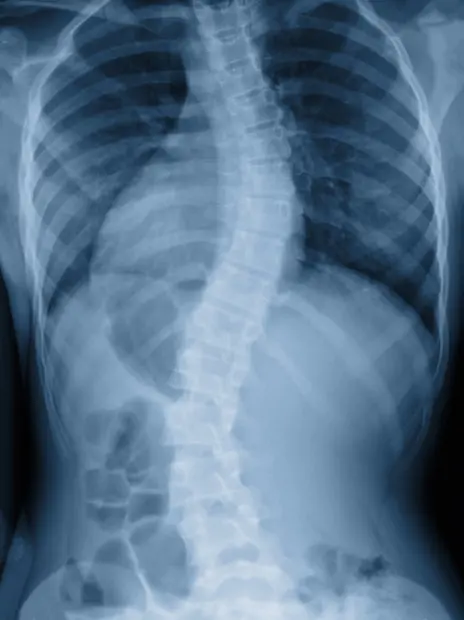

Scoliosis patients generally have an S or C shape to their spines when viewed on an x-ray. The spine curves sideways to the left or to the right. Nearly half of all cases have no discernible cause, but this can sometimes be good news. Patients with scoliosis generally experience uneven hip or shoulder alignments which may affect height/stature and how you carry your weight. They often experience dull aches around the spine, difficulty breathing, a twisted torso or rib cage and prominent shoulder blade exposure on one side or the other. It is abnormal for an adult to develop a severe spinal curve without a major injury or tumor though.